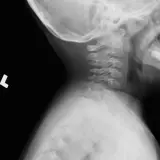

Over 2,100 interactive radiology cases, curated by radiologists for your level of training. Scroll, window, and view cases full screen — just like on PACS. Click linked findings in each writeup to jump straight to them on the image. Cases include sample reports, a focused discussion section, original illustrations, and videos.

Casos totalmente interactivos con las herramientas que esperaría de un PACS: scroll, ventana, zoom, pan, mediciones, ROI y modo de pantalla completa.

• Anotaciones enlazadas

Anotaciones extensas resaltan los hallazgos clave directamente sobre los casos. Haga clic en los hallazgos enlazados dentro de la descripción del caso para saltar a su ubicación exacta en el estudio.

Aprenda con eficiencia gracias a hallazgos de imagen anotados e ilustraciones